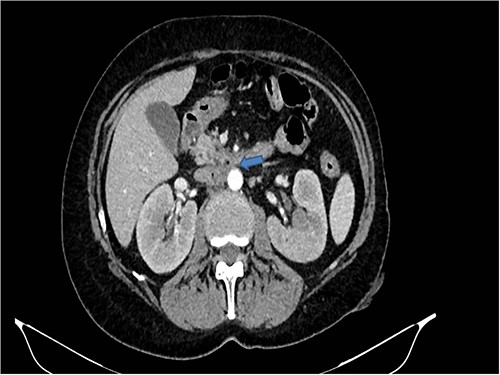

A 58-years-old woman arrived to our emergency department for fever (39.5°C) with chills and diffuse abdominal pain radiating to the back about 2 weeks. Her medical history included a hysteroannexectomy with sigmoid resection for an ovarian tumor that occurred 2 years earlier (Stage IIb) and adjuvant radiotherapy and traditional chemotherapy, subsequently followed by biological therapy with bevacizumab completed 6 months earlier. The patient was currently disease free and in follow-up. On admission, laboratory test showed a white cell count of 18 700 mL and microcytic anemia (hemoglobin level, 6.6 g/dL) with an increase in inflammation indices (CRP 26.2 mg/dl). Evidence of several digestive tract bacteria, including Enterococcus faecium, Escherichia coli and Weissella confusa, was disclosed by means of several hemocultures. A specific antibiotic therapy was started and blood transfusions were performed for the anemia found. Therefore, the patient underwent a chest and abdomen CT scan, which showed the presence of strong adherence between the IVC at the origin of the left renal vein and the third duodenal portion with air inside the vena cava and thrombotic-like hypodense material as for a DCF (Figs 1 and 2).

In coronal view the arrow points the air inside the vena cava and thrombotic-like hypodense material.